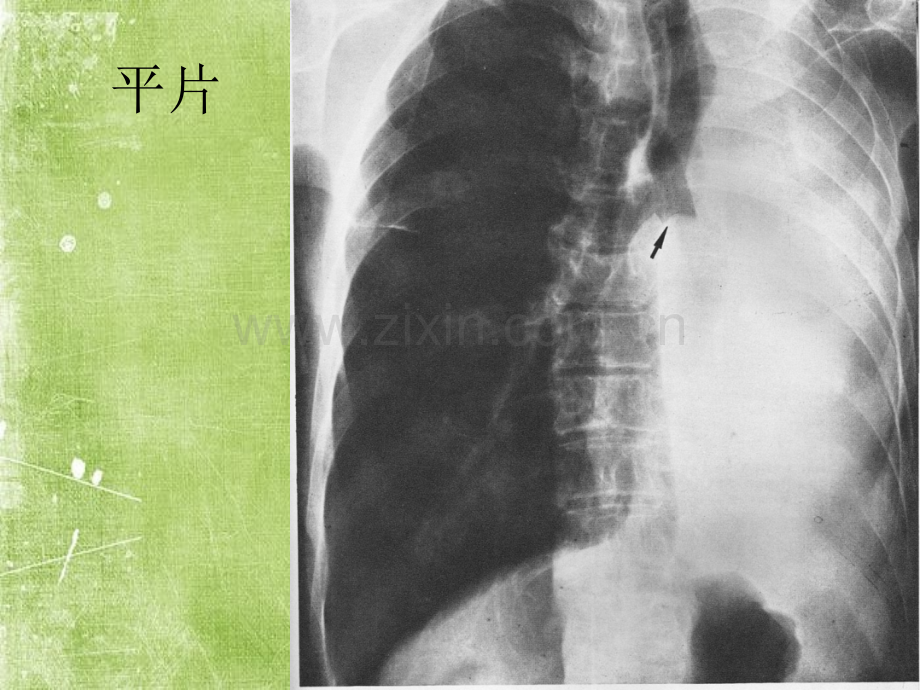

早期肺癌的CT诊断平片纯GGO 孤立、直径小于5mm不需要随诊孤立、直径大于5mm3月后复查。大的纯GGO大多数为侵袭性病变 多发小于5mm的边缘清晰的GGO,2年及4年后随诊 多发纯GGO,至少一个病变大于5mm,建议3月后复查,且长期随诊,至少随诊3年 有突出病灶的多发GGO。首次3月后复查,尤其是病灶内的实性成分大于5mm者。部分实性GGO实性成分大于5mm者,3月后复查